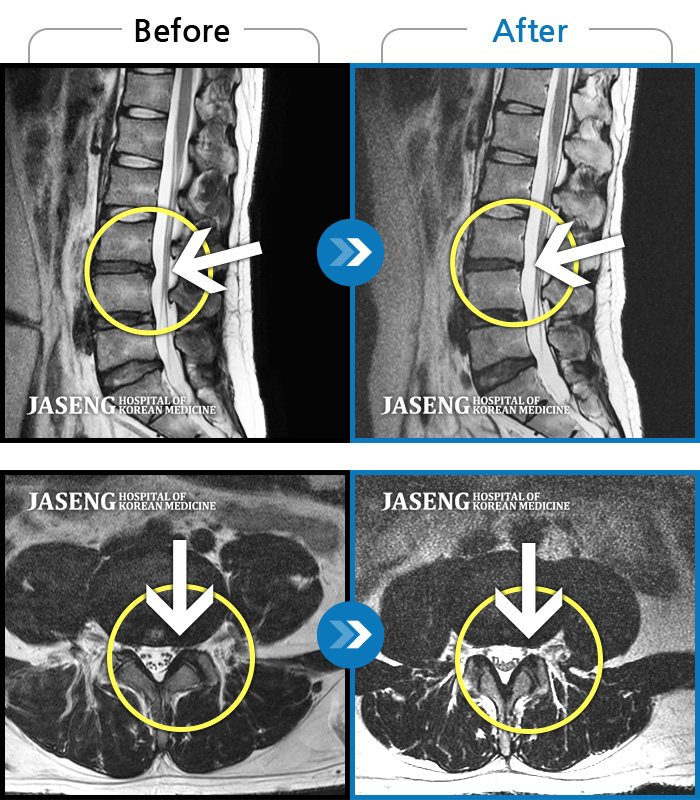

MRI 치료사례

스스로 침대에 오르내리지 못하고 심한 야간통으로 일상생활이 불가능했던 상태